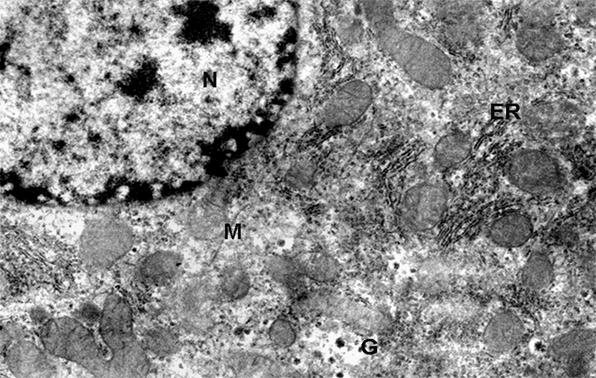

Phot. 1.

Electron micrographs of hepatocyte fragment of control group - 12 weeks old.

(N) nucleus, (ER) endoplasmic reticulum, (M) mitochondria, (L) lysosomes, x 8.500